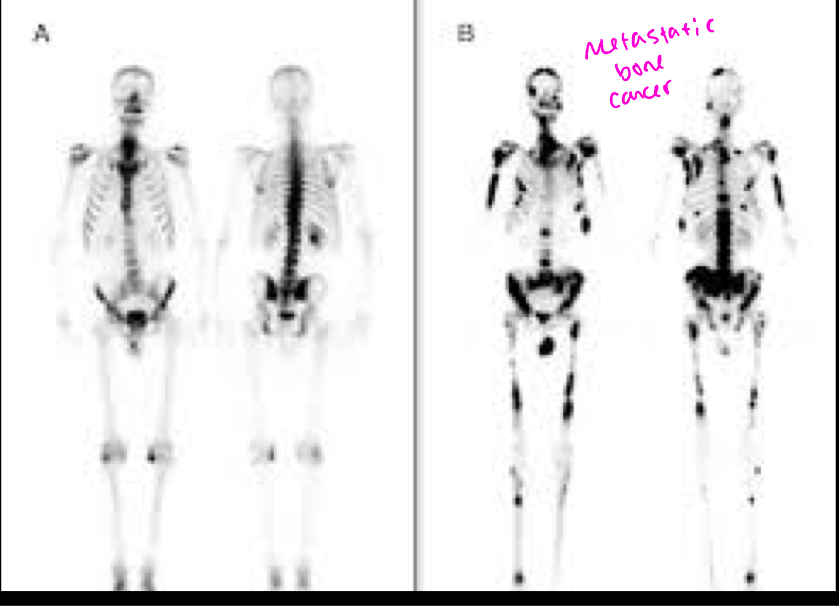

Normal bone scan vs abnormal bone scan with metastisis